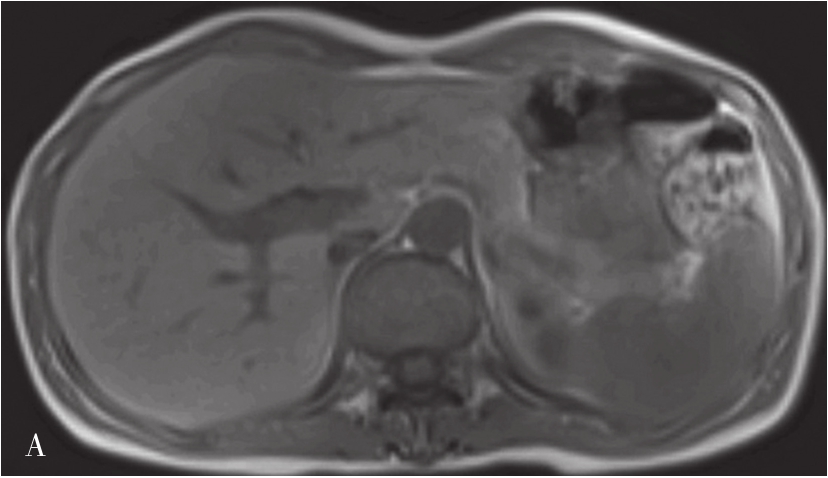

MRI图像,正常肝脏蛋白质含量丰富,自由水含量较少,肝组织的T 1 、T 2 弛豫时间短,T 1 WI呈中等强度的灰阶,与脊髓及胰腺相仿,肝脏信号相对高于脾脏及肌肉(图5-21-40A);T 2 WI则低于脾脏(图5-21-40B)。肝内血管和胆管在T 1 WI通常表现为低信号,T 2 WI胆管呈高信号。第二肝门处3根静脉在肝实质衬托下呈“鸡爪状”向腔静脉聚集。正常肝总管及左右肝管一般不被显示,在扩张情况下表现为门脉前方与之伴行的管道结构,信号略高于门脉。MRI上观察肝脏是否正常,一般要从肝脏形态、大小、信号是否异常,肝的分叶分段是否俱全、轮廓是否光整、表现是否光滑、肝裂是否增宽、质地是否细腻、信号是否均匀、血管纹理是否走行自然等多方面去评价。

图5-21-40 正常T 1 WI及T 2 WI图像

A.正常T 1 WI图像;B.正常T 2 WI图像